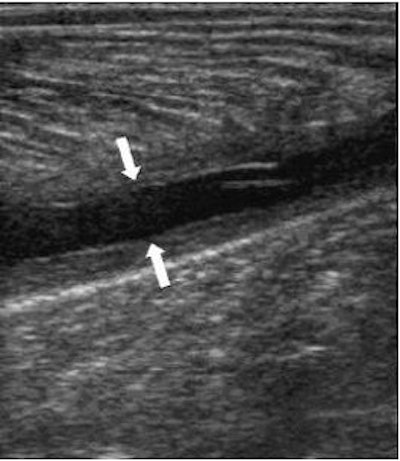

![]() |

| Tennis leg-related hematoma on ultrasound. Image courtesy of Dr. Ronald Adler, Hospital for Special Surgery, New York City. |

Beall agreed with Mintz, adding that sonographic evaluation of the gastrocnemius complex was useful if fluid was present or if the hematoma could be seen in the middle of the muscle.

But ultrasound should be used with caution, according to Major. "When there's hemorrhage present, it often doesn't look like a simple fluid collection (with ultrasound) and it has mixed echoes in it, so it can be a less straightforward diagnosis than with MRI," he said.